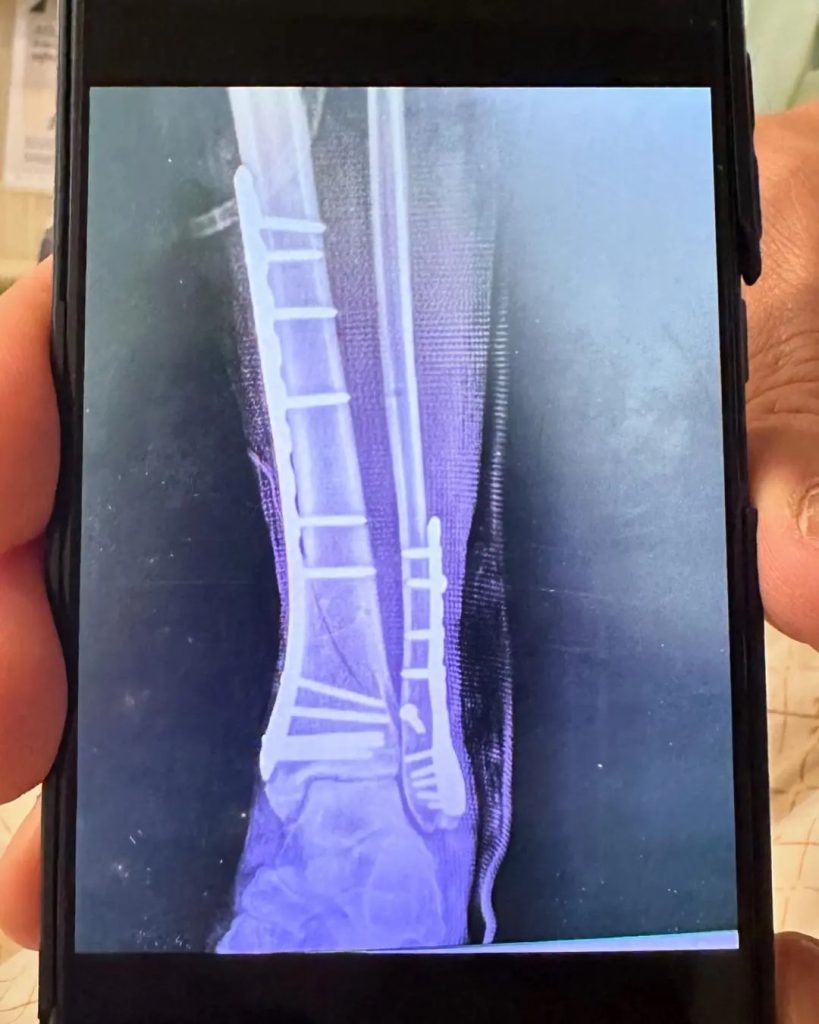

ทำเอาแฟน ๆ เป็นอดีตนางแบบชื่อดัง “โย ยศวดี” อย่างมาก หลัง เธอ เกิดอุบัติเหตุเนื่องจากมอเตอร์ไซค์ที่ตนซ้อนท้ายเจอถนนชำรุดและลื่นจึงทำให้ล้มคว่ำ ส่งผลให้ สาวโย ข้อเท้าหัก ต้องเข้าผ่าตัดทันที ซึ่ง เธอ ได้โพสต์รูปขณะนอนรักษาตัวอยู่โรงพยาบาลพร้อมแคปชันว่า “อุบัติเหตุเกิดขึ้นได้ทุกทีแค่ต้องมีสติและก้าวเดินต่อไป โย รถมอเตอร์ไซต์ล้มค่ะซ้อนมาด้านหลังทำให้ข้อเท้าข้างซ้ายหัก มันเป็นอุบัติเหตุเพราะว่าถนนชำรุดและลื่นมาก ตอนนี้กำลังจะเข้าผ่าตัดที่โรงพยาบาลสมิติเวช เชื่อว่าคุณหมอสามารถรักษาให้หายและกลับมาเดินปกติได้ในเร็ววันนี้ค่ะ พักและกายภาพ แปปเดียวละยอมรับว่าเสียใจเพราะต้องใช้เวลา2-3เดือน แต่ก็ได้กำลังใจจากคนรอบข้างมากมาย มันเกิดขึ้นแล้วก็ต้องทำใจ คิดบวกอย่างเดียว แล้วจะกลับมาฟิตใหม่เร็ว ๆ นี้แน่นอน รู้วิธีฟื้นตัวได้เร็วอยู่แล้ว ตอนนี้กำลังจะเข้าผ่าตัดแล้วค่ะ ขอกำลังใจหน่อยน้าา”